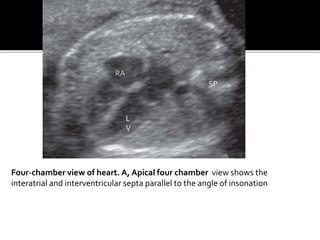

Four-chamber view of heart. A, Apical four chamber view shows the

interatrial and interventricular septa parallel to the angle of insonation

RA L V SP Four-chamber view ofheart. A, Apical four chamber view shows the interatrial and interventricular septa parallel to the angle of insonation